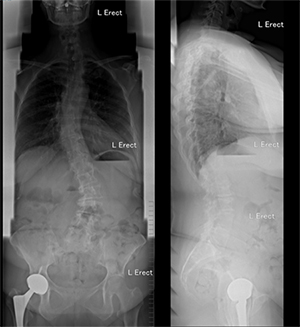

Deformity surgery is one of the more challenging procedures in spinal surgery and can account for long operative times and blood losses. Even among Fellowship-trained Deformity Surgeons, many studies show intraoperative adverse events and related postoperative complications rate of 10 to 15%. Significant blood loss in posterior spinal fusion (PSF) surgery for paediatric and adult scoliosis can cause haemodynamic complications and increases the incidence of allogeneic blood transfusion. The increased risk of intra-operative bleeding is related to the long incision, extensive soft tissue dissection, multi-level decompression surgery, decortication of bony surfaces and prolonged operative time.

To date, many strategies have been in use to attempt to reduce perioperative complications in adult deformity surgery. These include better preoperative planning strategies, intraoperative neuromonitoring, having a blood transfusion/cell saver strategy and staging surgeries.

Similar results were found in complex spine surgery studies. Halanski et al, Ames et al, Chan et al. reported that the involvement of two surgeons in corrective surgery for scoliosis was associated with reduced operative time, blood loss and the need for allogenic blood transfusion.

The Seattle spine team found that other complication rates were significantly lower as well when two consultant-level surgeons operated simultaneously on cases involving long fusions (16% vs. 52%). There were significantly lower return rates to the operating room during the perioperative 90-day period (0.8% vs. 12.5%), lower rates of wound infection requiring debridement (1.6% vs. 7.5%), lower rates of deep vein thrombosis/pulmonary embolism (3.2% vs. 10%), and lower rates of postoperative neurological complications (0.5% vs. 2.5%). The use of 2 surgeons experienced in spine deformity also helped achieve a decreased rate in major complications, decreased rate in premature case termination, and decreased rate of returns to the operating room within 30 days.

The mean operating time reported in literature for adult spinal deformity surgery involving 5 or more levels is around 300 to 360 minutes. Reducing operating time while maintaining strict adherence to good surgical technique and avoidance of intraoperative complications is key to good outcome for patients.